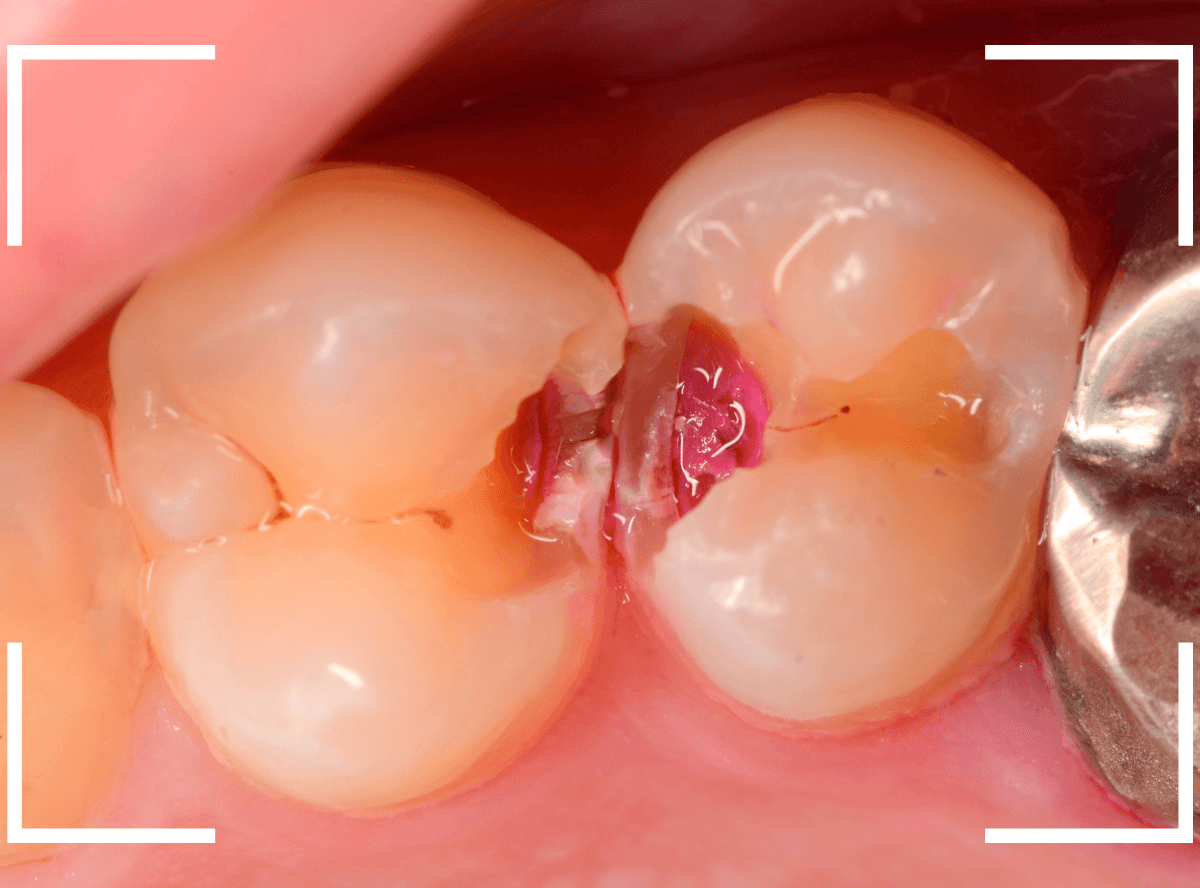

レジンを外して、う蝕検知液で確認します。

レジンの中で虫歯が進行していたのがわかります。

ある程度、虫歯を除去したところで、う蝕検知液で確認します。

赤く染まっている部分が虫歯です。

まだまだ虫歯が中で残っている状況で、かなり深い虫歯なのが確認できます。